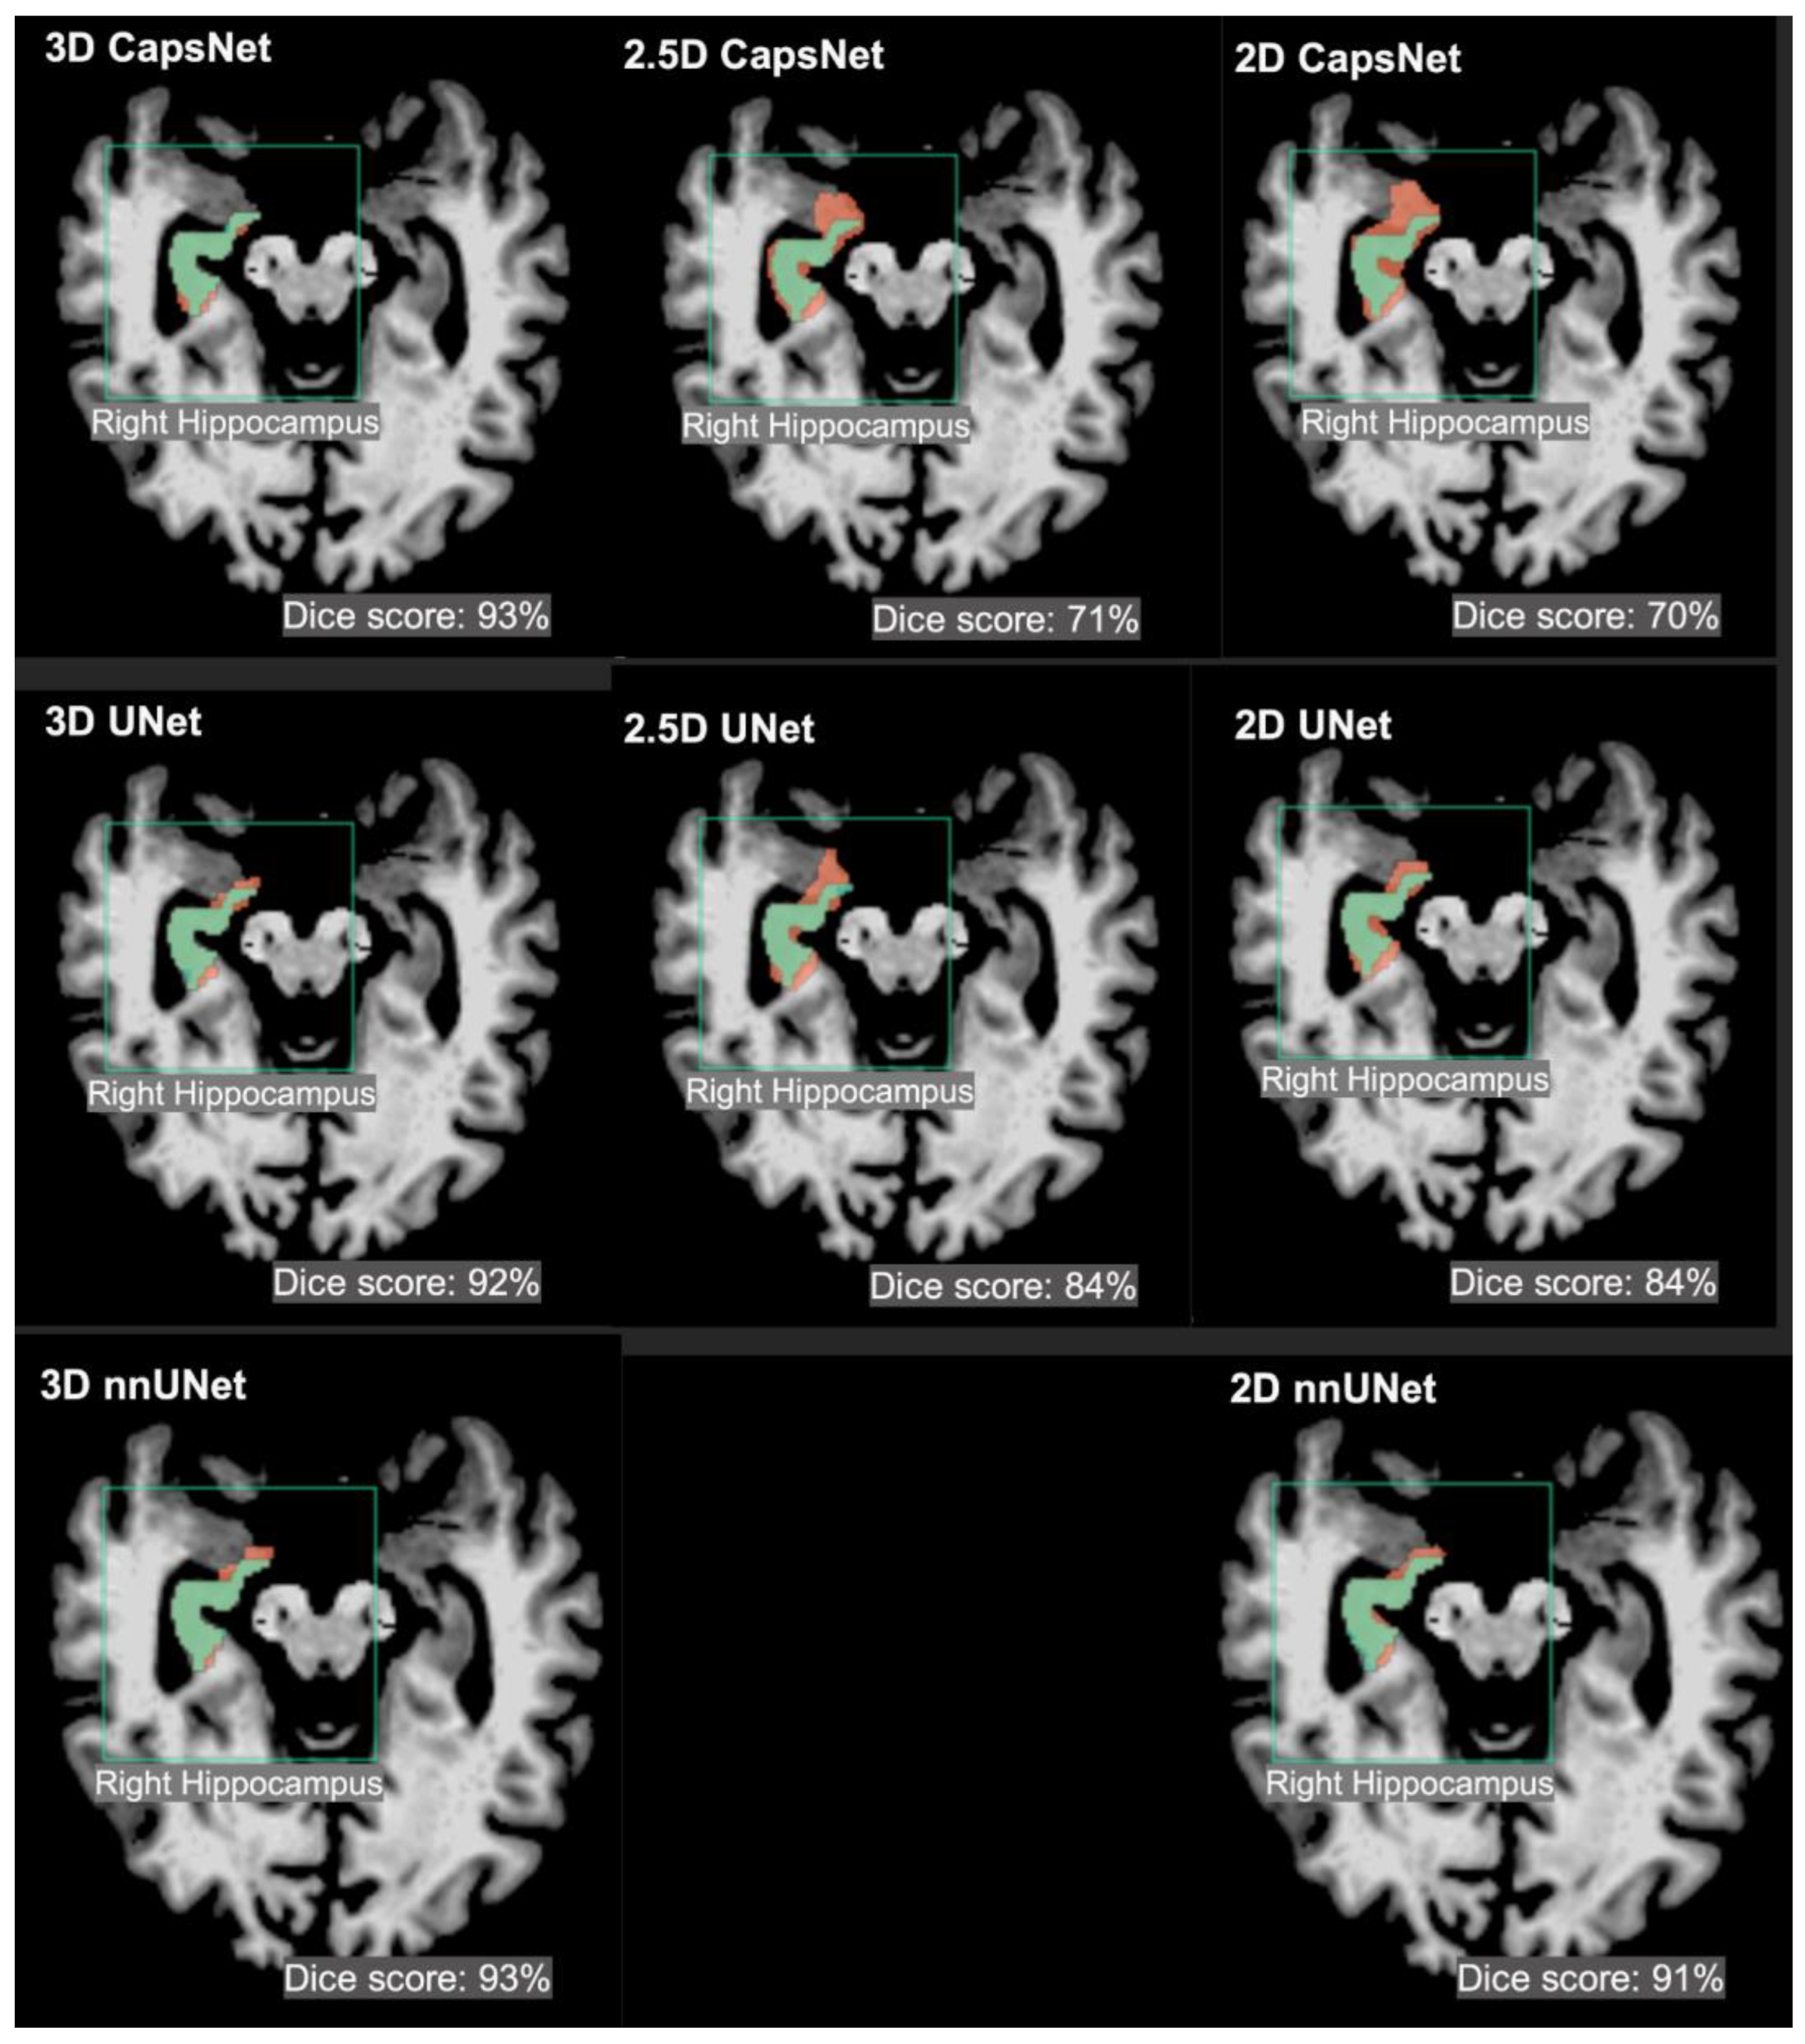

| Brain Structure | 3D Dice (95% CI) | 2.5D Dice (95% CI) | 2D Dice (95% CI) |

| 3rd ventricle | 95% (94 to 96) | 90% (89 to 91) | 90% (88 to 92) |

| Thalamus | 94% (93 to 95) | 76% (74 to 78) | 75% (72 to 78) |

| Hippocampus | 92% (91 to 93) | 73% (71 to 75) | 71% (68 to 74) |

| UNet | |||

| 3rd ventricle | 96% (95 to 97) | 92% (91 to 93) | 91% (89 to 91) |

| Thalamus | 95% (94 to 96) | 92% (91 to 93) | 90% (88 to 92) |

| Hippocampus | 93% (92 to 94) | 86% (84 to 88) | 88% (86 to 90) |